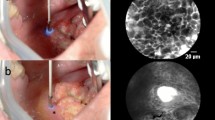

For 42 patients, 96 zones could be imaged (2.9 images per zone) and compared to final histology (HES section). The videos were of heterogeneous quality, mainly due to difficulties stabilizing the miniprobe for image acquisition (8 images/sec) during patient examination. As a consequence, 7.1% of the data acquired in tumor zones could not be presented to pathologists. In these cases, images were mainly composed of artifacts. However, 92.9% of recorded zones were presented to PT1 and PT2 and 64.3% were presented to PT3. The pathologists’ evaluation of the pCLE images in each zone was then based on recognition of architectural and cellular criteria. Importantly, PT1 considered that poor quality prevented 26.8% of the zones from vocal folds from being informative. When the head and neck pCLE images in a zone were considered by our pathologists to be of at least sufficient quality to allow evaluation, it was because the fluorescent dye had allowed morphological analysis of the images based on architecture, size of cells, and nuclei shape. Heterogeneous patent blue V staining and arbitrary dye loading resulted in limited visualization of cells and/or nuclei in some images. Despite this, images supplied information on the heterogeneous distribution of cancerous cells surrounded by inflammatory and/or fibrous stroma in precancerous or cancerous tissue (Fig. 2A and C). In contrast, regular cell distribution and homogeneous nuclei size distribution were visible in noncancerous zones (Fig. 2D). Keratinization abnormalities such as keratin pearls could be recognized by pathologists on pCLE images, helping to distinguish well-differentiated SCC from normal squamous epithelium.

All pathologists had equivalent concordance rates in the tumor zone (from 69.6 to 74.8%) and anterior margin zone (50%), independently of previous experience in optical biopsy (Table 2). Figure 3 presents typical pCLE images of cancerous tissue (Fig. 3A and B), and squamous (Fig. 3C and D) and respiratory epithelium (Fig. 3E) that PT1 interpreted in concordance with the histological diagnosis.

We analyzed discrepancies according to tumor location for PT1, the most experienced pathologist in our study (Table 4). False negatives and false positives mainly occurred when imaging vocal folds or the tongue. Figure 4 presents pCLE images for which there was a discrepancy between PT1’s interpretation and the histological diagnosis. A poorly differentiated HNSCC (histological diagnosis) was misclassified as respiratory epithelium (Fig. 4A) and a well-differentiated HNSCC was misclassified as noncancerous tissue (Fig. 4B). Respiratory epithelium was misclassified as low-grade dysplasia (Fig. 4C) and high-grade dysplasia/in situ carcinoma wrongly classified as squamous epithelium (Fig. 4D).

Typical pCLE images interpreted by pathologist 1 that had discrepancies between interpretation and final histological diagnosis: A invasive poorly differentiated HNSCC wrongly interpreted as respiratory epithelium; B respiratory epithelium wrongly interpreted as low-grade dysplasia; C noncancerous tissue wrongly interpreted as invasive well-differentiated HNSCC; and D high-grade dysplasia/in situ carcinoma wrongly interpreted as squamous epithelium